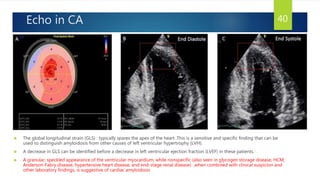

Echo in CA

 The global longitudinal strain (GLS) : typically spares the apex of the heart .This is a sensitive and specific finding that can be

used to distinguish amyloidosis from other causes of left ventricular hypertrophy (LVH).

 A decrease in GLS can be identified before a decrease in left ventricular ejection fraction (LVEF) in these patients.1

 A granular, speckled appearance of the ventricular myocardium, while nonspecific (also seen in glycogen storage disease, HCM,

Anderson-Fabry disease, hypertensive heart disease, and end-stage renal disease) ,when combined with clinical suspicion and

other laboratory findings, is suggestive of cardiac amyloidosis

40